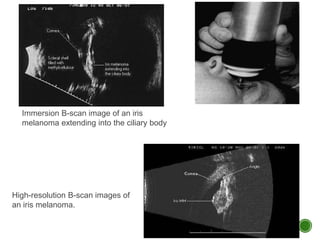

Immersion B-scan image of an iris

melanoma extending into the ciliary body

High-resolution B-scan images of

an iris melanoma.